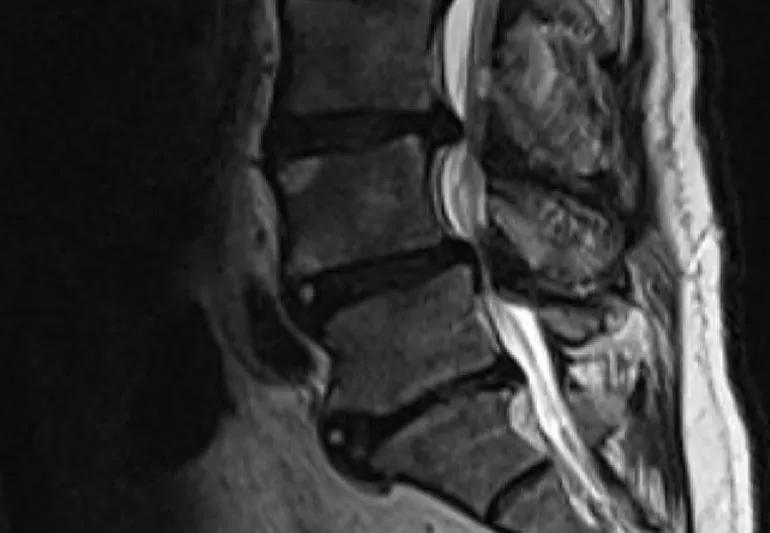

To find out if you are a candidate for this surgery, a set of imaging studies will be done. These include an X-ray of the spine while standing to look at the position of the bones and magnetic resonance imaging (MRI) to get a more detailed image of the nerves and soft tissues.

Spinal stenosis occurs when there is narrowing of the spinal canal or the neural foramen. This can put pressure on nerves. When this happens in the low back, it can impinge on the sciatic nerve, which extends from the low back down the leg. Common symptoms of sciatica are sharp pain, numbness, tingling and weakness in the buttocks and/or leg.

If nonsurgical measures fail to relieve symptoms of spinal stenosis, a surgical procedure called laminectomy (also referred to as decompression) can be done. A portion of the vertebra called the lamina is removed, along with any bone spurs or ligaments that may be causing the narrowing. The procedure makes more room for the nerves, thus relieving symptoms.

“The two most common causes of instability are degenerative spondylolisthesis and scoliosis,” says Dr. Savage. With spondylolisthesis, a vertebra has slipped forward or backward in relation to the adjacent vertebra. Scoliosis is a rotational curvature of the spine, which can occur in adults over time as a result of degeneration of disks. These conditions can worsen symptoms of spinal stenosis.